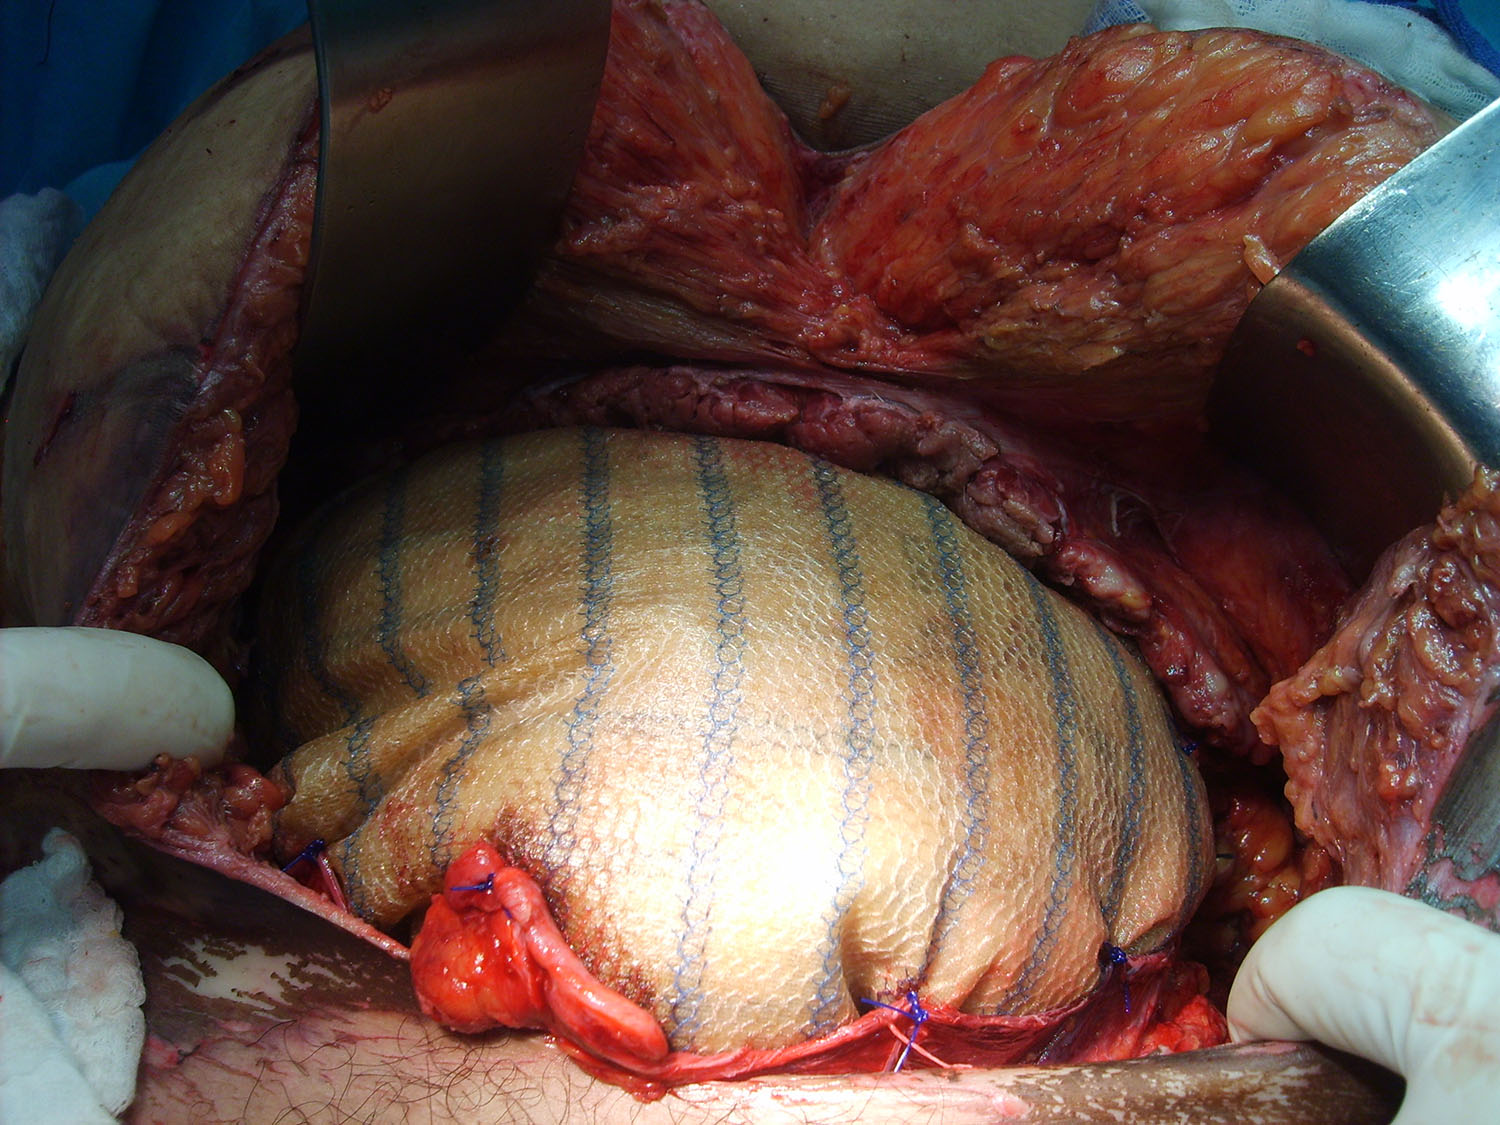

Luego de estabilizada la paciente y al cuarto día de la cirugía del abdomen abierto se lleva la paciente al quirófano. Se constata abdomen con escaso liquido serohemático y asas intestinales sin compromiso vascular por lo que se decide cerrar el abdomen. Es dificultosa la tarea de contener las asas intestinales en la cavidad abdominal debido a la ausencia de pared lateral. Se decide el decolamiento del colon derecho e izquierdo a fin de lograr un espacio para colocar la prótesis, es decir generar un espacio real con el peritoneo para introducir la malla. La sugerencia adecuada del Dr Zorraquino es imposible de realizar, la enferma presenta una retracción importante de los músculos rectos que determinan una cavidad abdominal que supera ampliamente los 900 cm². Se coloca dos mallas de proceed 30 x 30 intraperitoneal fijadas con puntos al espesos total de los remanentes musculares y sobre la misma una malla de prolene 30 x 30 fijada abajo al pubis y a ambas crestas ilíacas y por arriba al plano aponeurótico de los rectos y Oblicuo mayor. Se deja piel y celular abierto. Vuelve a Cuidados Intensivos.

Estimado Dr Reyes, aprecio tus comentarios, nosotros no disponemos de mallas biológicas, que si creo hubiesen sido de utilidad en este caso.Con respecto a colocar malla de polipropileno sobre la proceed, fué para tratar de darle más contención al contenido abdominal, por eso esa prótesis la fijamos al pubis y a las crestas ilíacas que estaban totalmente a la vista, según mostramos en algunas fotos.